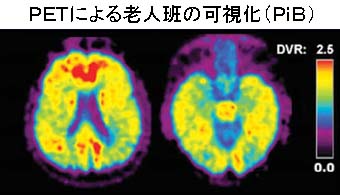

■上記のうち、PET検査においては主にベータアミロイドの蓄積である老人班を可視化して、病気の進行度を診断します。 近年においては、タウというタンパク質が神経細胞内に形成する構造物である、神経原線維変化が神経障害を起こすことが知られており、タウの蓄積状態を可視 化することにより、確実な診断を行うことができると考えられております。

■ 低侵襲性の診断法のひとつとしてPETがあります。これは低レベルの放射能を結合した化合物を体内に入れ、化合物の行方を画像化する装置です。これまでに アルツハイマー病の診断のために、数種類のPET化合物が開発され診断に用いられています。しかし、現時点で利用できるPET化合物には一長一短があり、 アルツハイマー病の確定診断が可能なPET化合物は存在しません。左図は、ピッツバーグ化合物(PiB)を用いたPETにより老人班の画像化を行った例で す。脳全体に老人班が広がっていることがわかります。